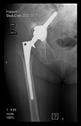

The radiological examination allowed us to verify the close bone-to-implant contact and the unchanged position of the implant during follow-up.

In all the cases operated with the above-described targeting procedure, the stems of the cups remained between the cortical bone surfaces without perforation of the linea terminalis, as shown by postoperative radiographs. There were no complicated surgical situations. In 16 cases, the wound healings were uneventful, and the hips were able to bear weight again after postoperative rehabilitation.

The only patient who suffered an infection healed after the removal of the implant. This complication rate is known and in line with accepted values.

One septic complication occurred. This complication rate is consistent with other revision techniques. In this case, the implant had to be removed, and the patient remained in Girdlestone condition. In such cases, removal of the implants and, of course, surgical debridement and antibiotic treatment are essential. The condition after resection is called Girdlestone’s condition. We had no other complications or unexpected outcomes.

At the time of the manuscript edition, some cases reported in this study were still in the early postoperative period. Even the shortest 10-month follow-up means that patients’ wound healing was uninterrupted, and the implant was securely fixed. By this time, patients are beyond successful rehabilitation. Of course, as with all such patients, monitoring will continue at annual check-ups. Report on the mid and long-term outcomes, gait analysis, and subjective assessments of patients is planned.